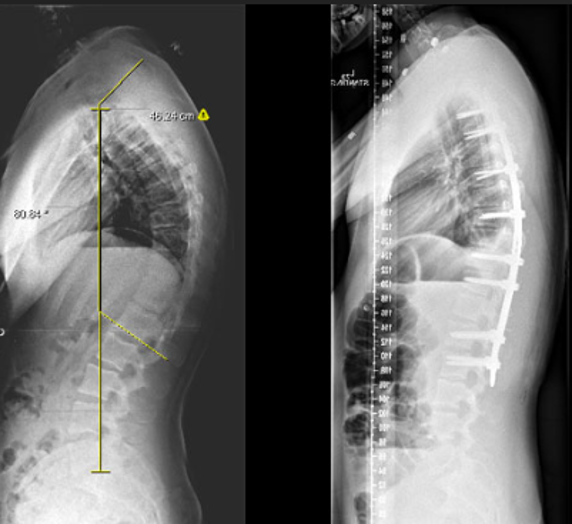

Spinal Deformity Correction (Scoliosis and Kyphosis)

Correcting abnormal spinal curvatures for better alignment and function.

Surgery to straighten and stabilize an abnormally curved spine using rods, screws, and fusion.

Curves are corrected with rods and screws. The bones are fused to maintain correction permanently.

- Straighter spine and improved appearance

- Better body balance and posture

- Relief from pain and, in some cases, improved breathing